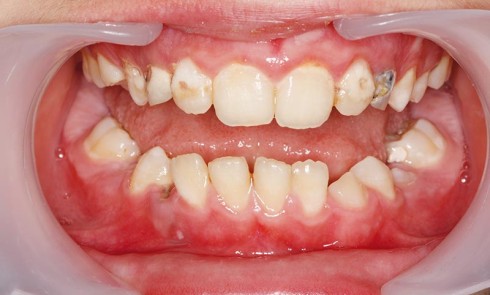

Article réservé à nos abonnés Exemple d’urgence La carie précoce de la petite enfance

Les dents sont affectées dans l’ordre chronologique de leur éruption, à l’exception des incisives mandibulaires qui, protégées par la langue...